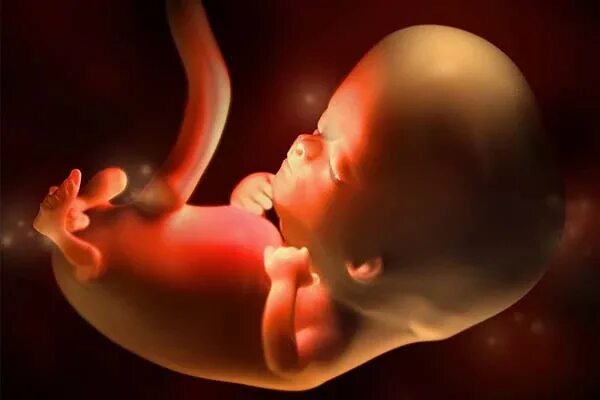

10 недель какие ощущения